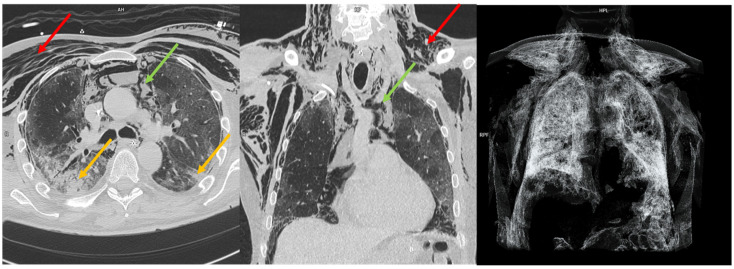

背景:麦克林效应最近在COVID-19 ARDS人群中显示出对气压创伤的高阳性预测价值。然而,关于没有SARS-CoV-2感染的ARDS人群的证据较少。我们的目的是分析COVID-19和非COVID-19 ARDS受试者,以评估Macklin效应在预测两组气压损伤发展方面的敏感性和特异性。方法:回顾性分析2018年1月至2022年11月在本中心收治的ARDS患者。经验丰富的放射科医生在胸部计算机断层扫描中检查了麦克林效应的存在。然后根据麦克林效应的存在与否将受试者分为两组,以评估其对气压创伤的预测能力。最后,我们分析了麦克林效应和气压创伤对重症监护病房和住院死亡率的影响。结果:我们分析了225例患者;在44名受试者中观察到麦克林效应。在我们的队列中,麦克林效应在预测气压损伤方面的敏感性为44.6%,特异性为90.6%。在排除COVID-19 ARDS病例后,麦克林效应的敏感性为34.7%,特异性为93.6%。尽管如此,在我们的人群中,麦克林效应的存在或气压创伤的发生并未导致ICU或住院死亡率的增加。结论:我们的分析强调,麦克林效应在预测气压创伤方面具有高特异性,但敏感性较低;此外,气压创伤的发生并不影响死亡率,这可能是由于排除了轻度至中度ARDS和纳入了大量ECMO受者。最后,麦克林效应在ARDS早期出现,可能作为肺衰弱的早期指标,可能成为转介到ARDS高级治疗中心的附加标准。

Background: The Macklin effect recently demonstrated a high positive predictive value for barotrauma in the COVID-19 ARDS population. However, there was less evidence available regarding the ARDS population without SARS-CoV-2 infection. We aim to analyze COVID-19 and non-COVID-19 ARDS subjects to assess the sensitivity and specificity of the Macklin effect in predicting the development of barotrauma in both groups. Methods: We retrospectively analyzed subjects with ARDS admitted to our center from January 2018 to November 2022. Experienced radiologists examined the presence of the Macklin effect on chest computed tomography scans. Subjects were then divided into two groups based on the presence or absence of the Macklin effect to assess its predictive power regarding barotrauma. Finally, we analyzed the impact of the Macklin effect and barotrauma on Intensive Care Unit and in-hospital mortality. Results: We analyzed 225 patients; the Macklin effect was observed in 44 subjects. In our cohort, the Macklin effect exhibited a sensitivity of 44.6% and a specificity of 90.6% in predicting barotrauma. After excluding the COVID-19 ARDS cases, the Macklin effect showed a sensitivity of 34.7% and a specificity of 93.6%. Nonetheless, in our population, the presence of the Macklin effect or the occurrence of barotrauma did not lead to increased ICU or in-hospital mortality. Conclusions: Our analysis highlighted that the Macklin effect demonstrates high specificity in predicting barotrauma but a low sensitivity; moreover, the development of barotrauma did not impact mortality, possibly due to the exclusion of mild to moderate ARDS and the inclusion of a significant number of ECMO recipients. Finally, the Macklin effect appears early during ARDS and may serve as an early indicator of lung frailty, potentially becoming an additional criterion for referral to centers for advanced ARDS treatment.